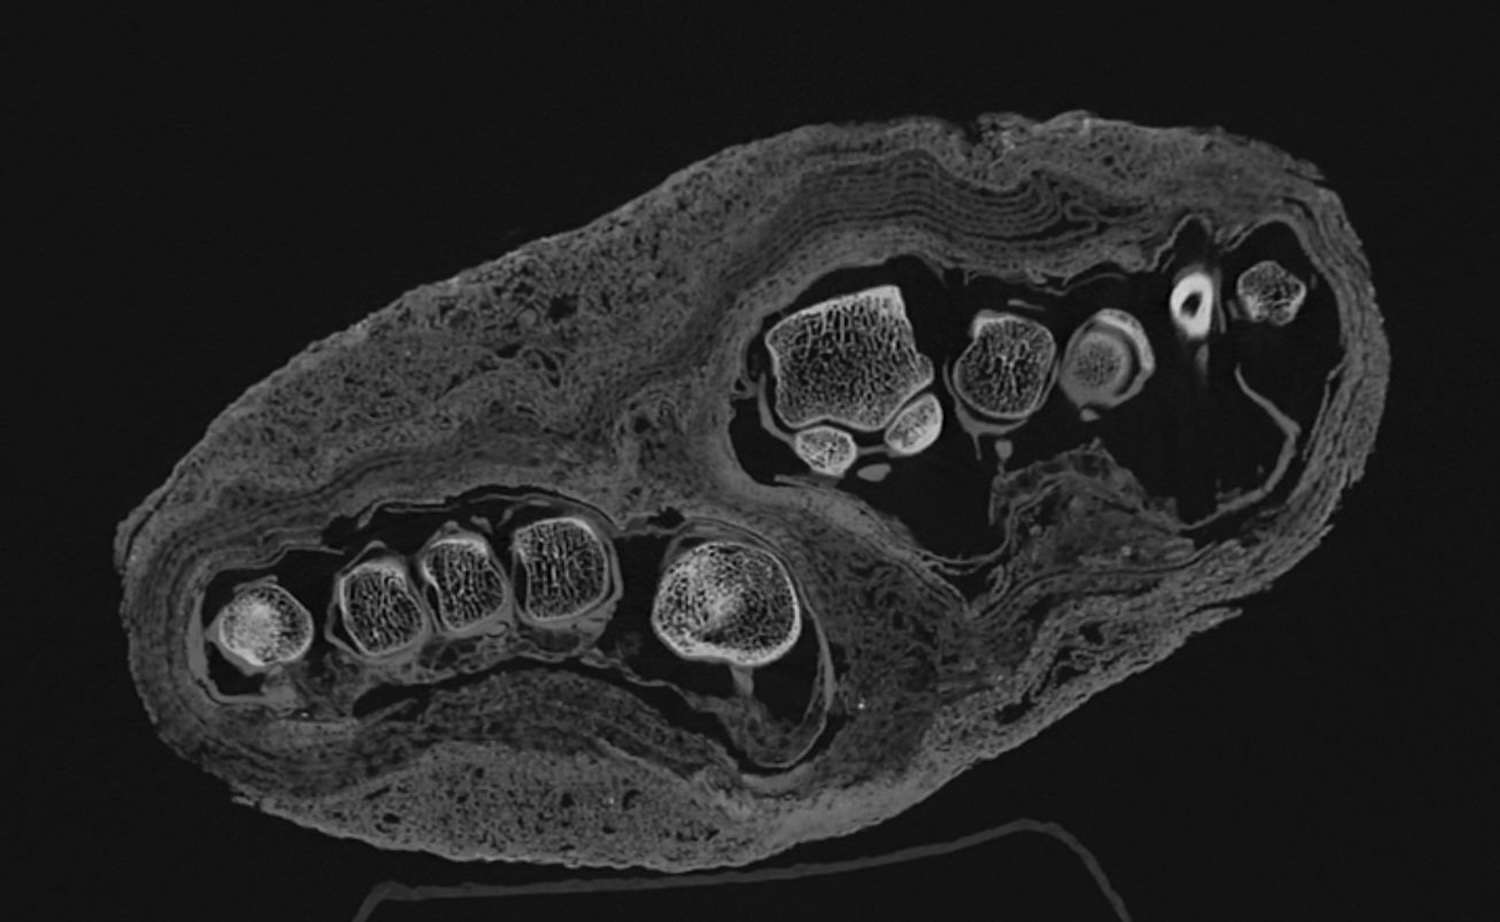

Take a collection of mummy fragments housed at the MNMKK Semmelweis Museum of Medical History in Budapest, Hungary. Curators have housed the archaeological discoveries since the institution opened in 1965, and at least some of the mummies are over 2,300 years old. But apart from the radiocarbon dating, they lacked the technological capabilities to safely study them. However, researchers can finally see the remains with impressive clarity thanks to the recent installation of a high-resolution CT scanner.

The post-mortem imaging team also looked at teeth, two heads’ skull sutures, and an individual’s partial limbs. In the latter case, they now think the person was relatively young and suffered from osteoporosis, but they remain unsure about the cause. That said, the museum team is confident that these findings are only the beginning.